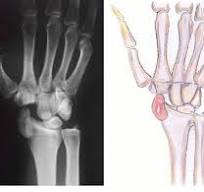

Wrist dislocation